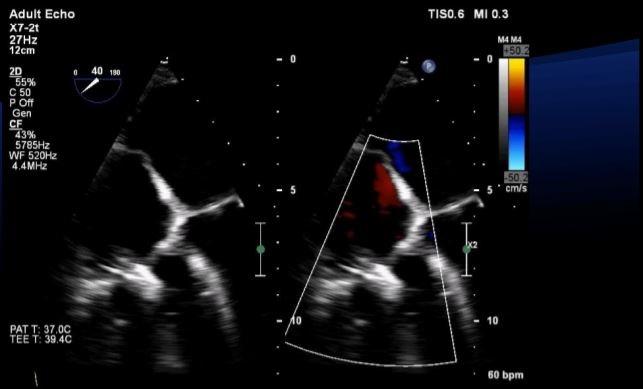

Photo Credit: Rebecca Hahn. Intraprocedural Imaging For Tricuspid Valve Interventions. Presented at: ECHO 2018. April 20, 2018. New York, NY.